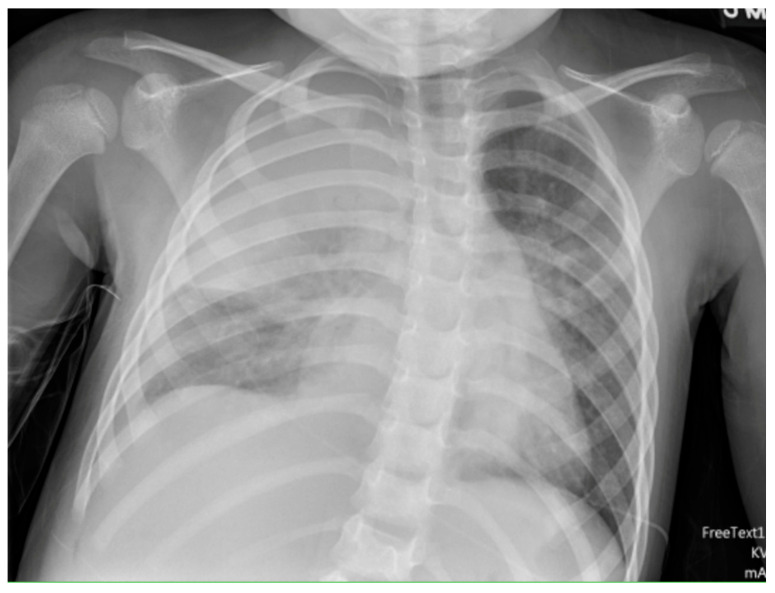

坏死性肺炎是小儿肺炎的严重并发症,以肺实质液化和空化为特征。肺炎链球菌和金黄色葡萄球菌是最受影响的微生物。肺炎支原体是一种越来越被认识到的病原体,特别是在亚洲,铜绿假单胞菌主要见于较高比例的复杂慢性疾病患者。临床表现通常包括发烧、呼吸窘迫和对标准抗生素治疗无效。这些患者更有可能以积液或脓胸的形式累及胸膜,并且更需要呼吸支持。诊断通常是通过胸片、肺超声和胸部计算机断层扫描的组合。治疗主要是通过长时间静脉注射抗生素覆盖上述微生物,尽管经常需要使用纤维蛋白溶解剂胸腔引流。手术干预通常保留在顽固性病例,最初的纤溶治疗失败。尽管早期识别和适当的管理对于减少病程和发病率是必要的,但短期和长期预后通常是有利的。

Necrotizing pneumonia is a serious complication of pediatric pneumonia, characterized by liquefaction and cavitation of the lung parenchyma. Streptococcus pneumoniae and Staphylococcus aureus are the most implicated organisms. Mycoplasma pneumoniae has been an increasingly recognized pathogen, especially is Asian and Pseudomonas aeruginosa is mainly noted in a higher percentage of patients with complex chronic conditions. Clinical presentation typically includes fever, respiratory distress, and failure to respond to standard antibiotic therapy. These patients are more likely to have pleural involvement in the form of effusion or empyema and a higher need for respiratory support. Diagnosis is typically through a combination of chest radiographs, lung ultrasound, and chest computed tomography. Management is primarily via prolonged intravenous antibiotics that cover the above organisms, though pleural drainage with fibrinolytics is often required. Surgical intervention is often reserved for refractory cases that fail initial fibrinolytic therapy. Prognosis is usually favorable in the short and long term, though early recognition and appropriate management are imperative to reduce the duration of illness and morbidity.